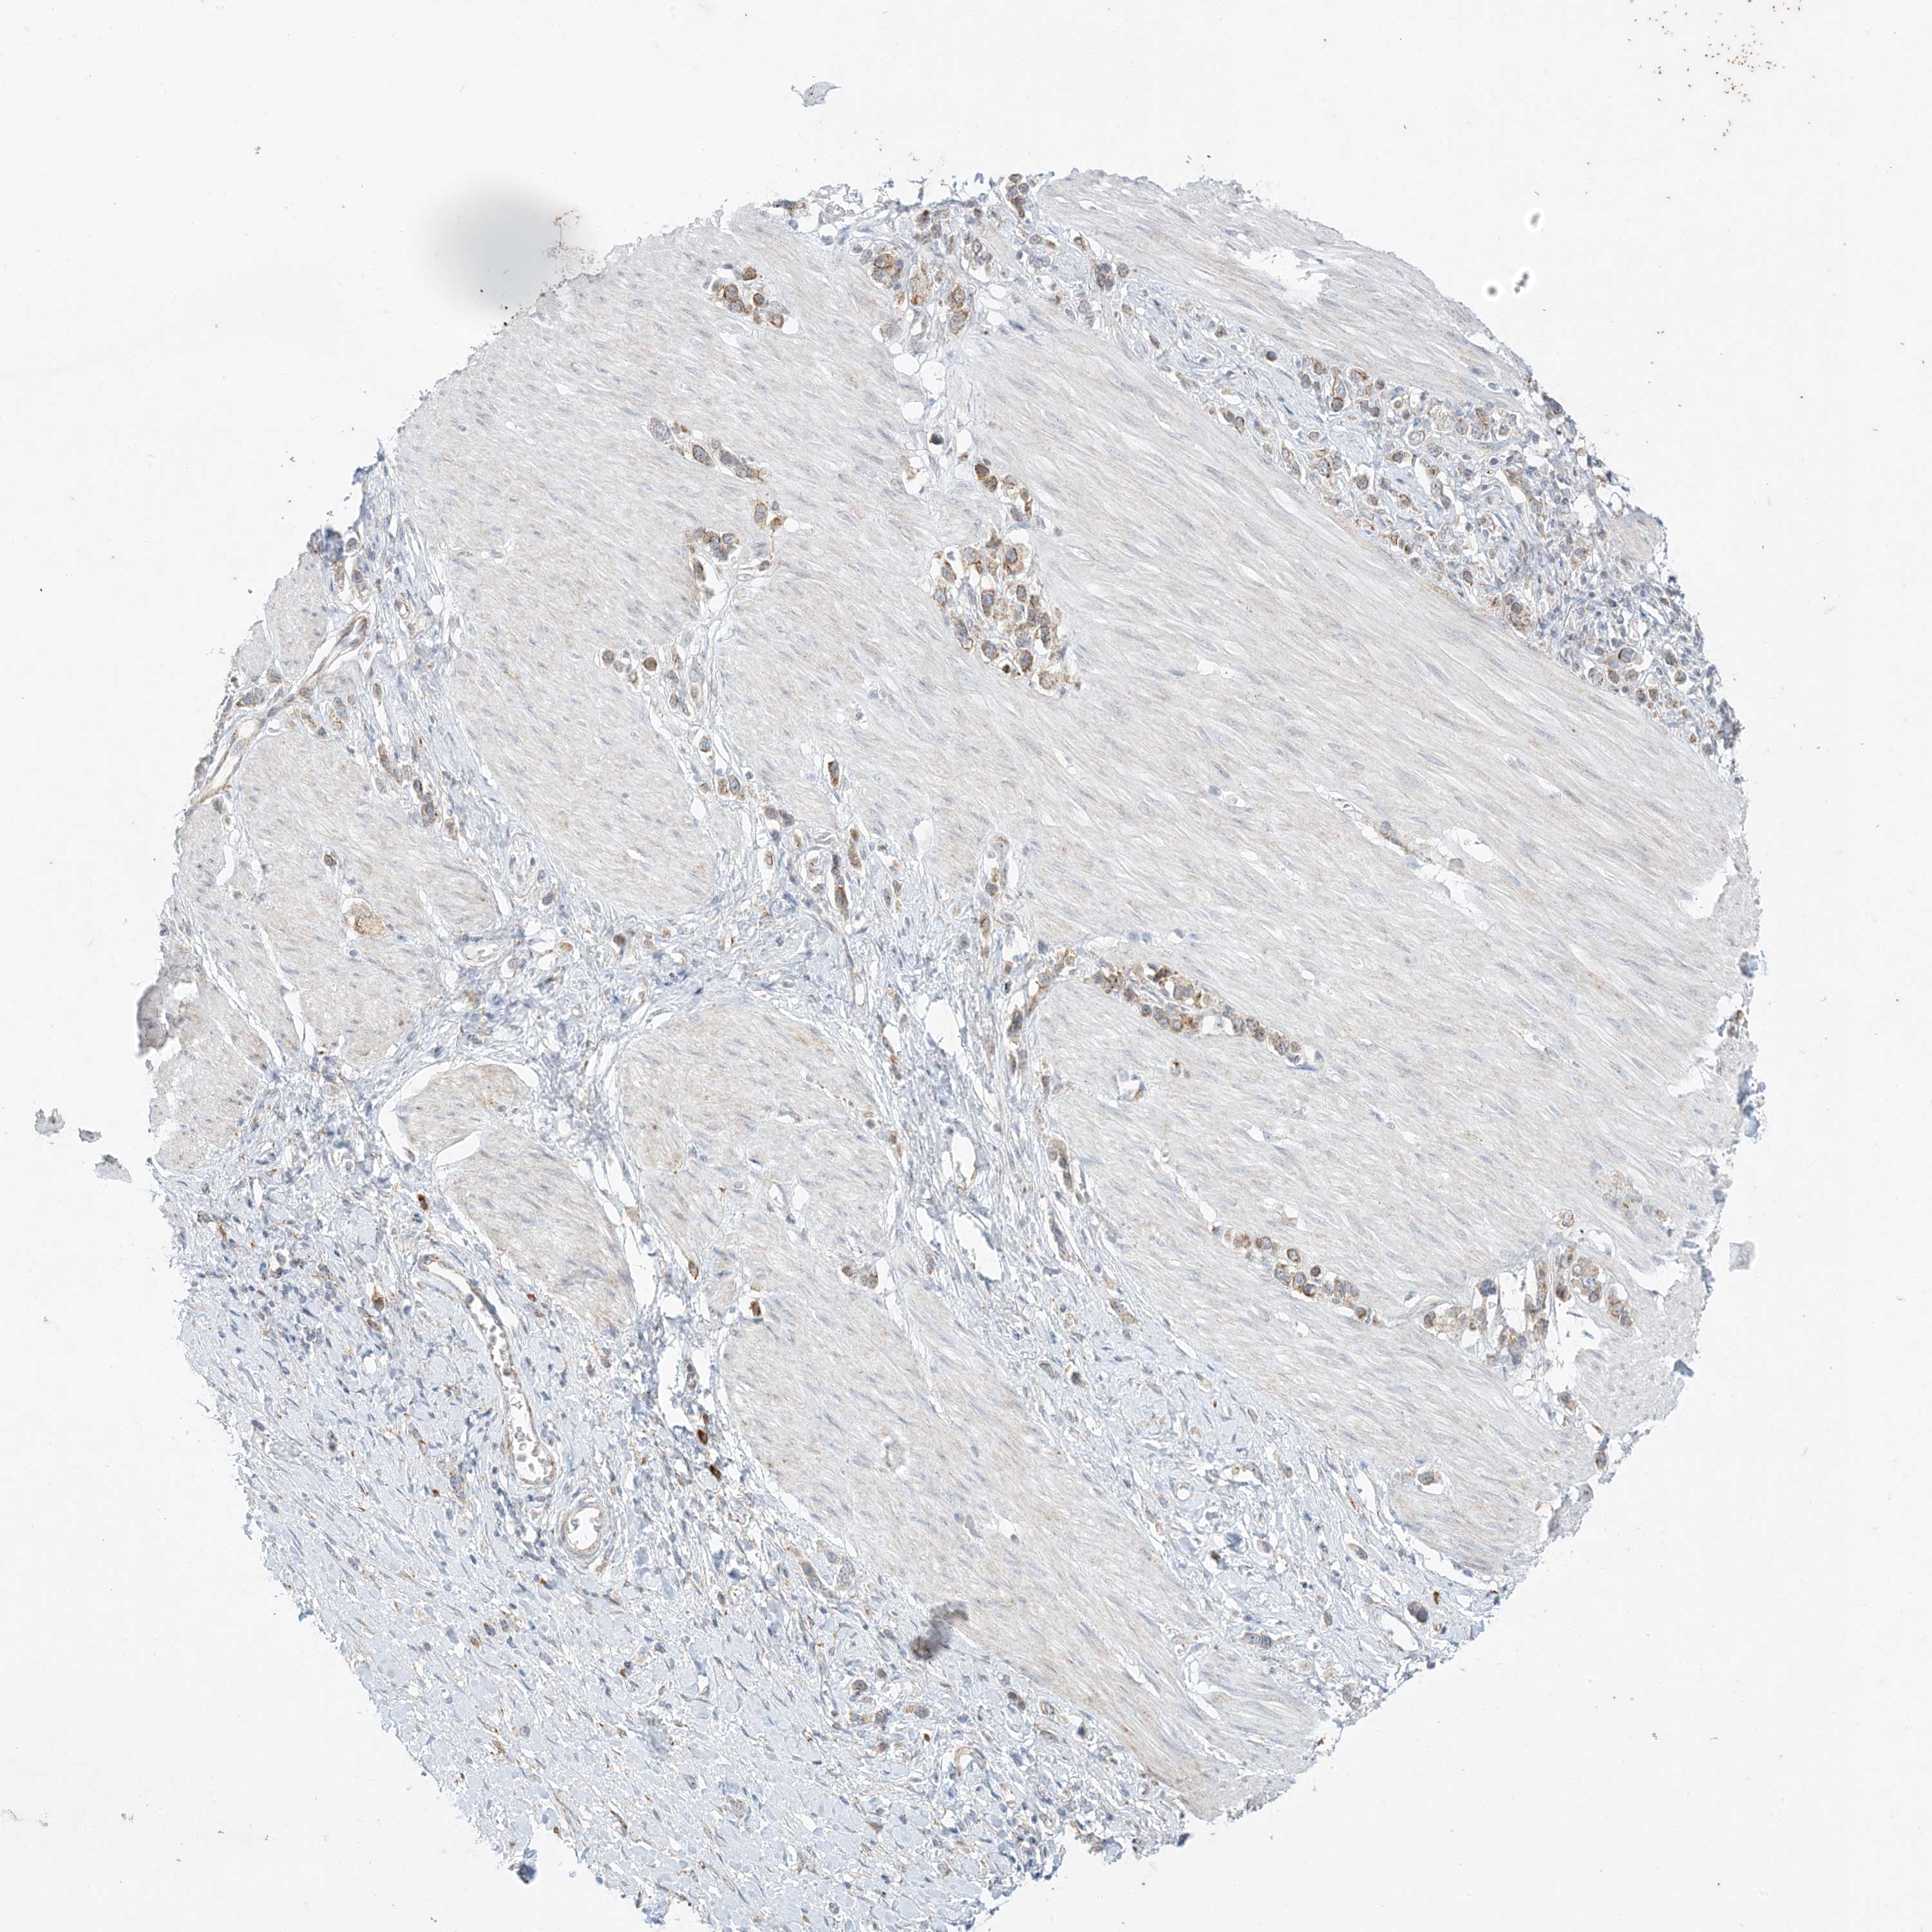

STOMACH CANCER - Protein expressioni

A mouse-over function shows sample information and annotation data. Click on an image to view it in a full screen mode. Samples can be filtered based on level of antibody staining by selecting one or several of the following categories: high, medium, low and not detected. The assay and annotation is described here.

Note that samples used for immunohistochemistry by the Human Protein Atlas do not correspond to samples in the TCGA dataset.

Antibody stainingi

Antibody staining in the annotated cell types in the current human tissue is reported as not detected, low, medium, or high, based on conventional immunohistochemistry profiling in selected tissues. This score is based on the combination of the staining intensity and fraction of stained cells.

Each image is clickable and will lead to virtual microscopy that enables deeper exploration of all samples and also displays staining intensity scores, fraction scores and subcellular localization as well as patient and tissue information for each sample.

Antibody HPA047820

Antibody CAB035994

Staining

High

Medium

Low

Not detected

Intensity

Strong

Moderate

Weak

Negative

Quantity

>75%

75%-25%

<25%

None

Location

Nuclear

Cytoplasmic/membranous

Cytoplasmic/membranous,nuclear

Adenocarcinoma, NOS